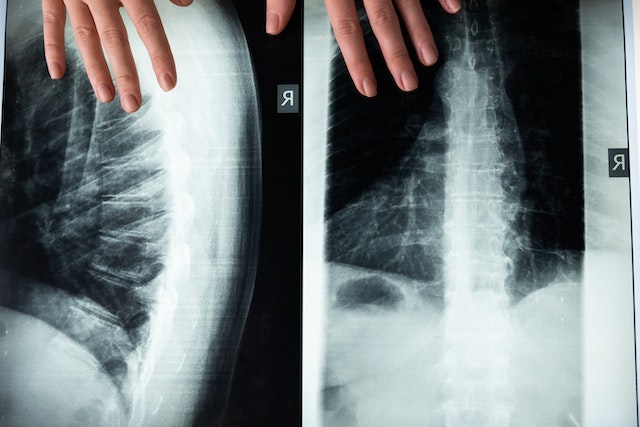

Prelomi pršljenova – koji se takođe nazivaju prelomi kičme – izazivaju bol u leđima i najčešći su kod osoba sa osteoporozom. Ovi prelomi mogu biti rezultat i jednostavnih zadataka kao što su obavljanje kućnih poslova.

Bol u kostima je najčešći simptom. Međutim, mnogi ljudi sa Pagetovom bolešću nemaju simptome. Stanje se često otkriva rendgenskim snimkom za drugu svrhu. Najčešće pogađa kičmu, karlicu, butnu kost (butinu), humerus (nadlaktica) i kosti lobanje.